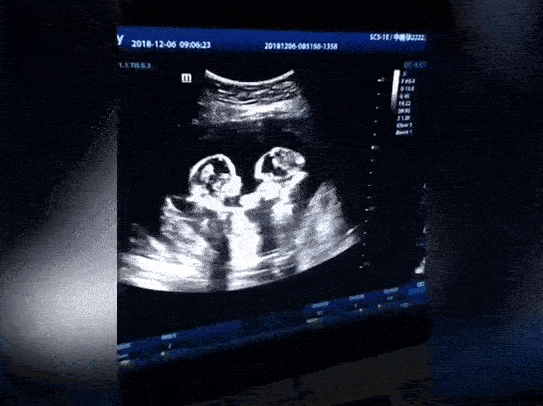

Theo China Daily đưa tin, đây là cặp song sinh đơn bào (hay còn gọi là Mo-mo) khi chúng chia sẻ cùng 1 túi ối và nhau thai trong bụng mẹ. Những trường hợp như vậy chỉ xảy ra với tỉ lệ cực kỳ nhỏ, khoảng 1/35.000-60.000 ca mang thai. Không chỉ là cặp song sinh hiếm lạ, cả 2 đứa trẻ còn sớm trở thành ngôi sao mạng xã hội khi chúng không thể chờ được đến lúc chào đời để tranh cãi với nhau. Ở tháng thứ 4 của thai kỳ, hình ảnh siêu âm cho thấy 2 bé như thể đang xảy ra mâu thuẫn, thậm chí quơ tay đánh nhau. Điều này dự báo nhiều khả năng chúng sẽ chí chóe với nhau cả ngày, bố mẹ nên chuẩn bị tinh thần.

2 chị em thay nhau đánh người còn lại.

Bố của 2 đứa trẻ, anh Tao, 28 tuổi, tỏ ra thích thú trước hành động của 2 cô con gái. May mắn là chúng không phải lúc nào cũng đánh nhau. Trước đây, anh Tao cũng từng thấy cặp song sinh ôm nhau vô cùng tình cảm trong một lần siêu âm khác.